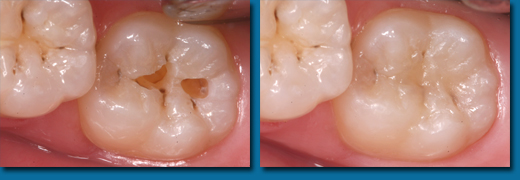

子供の出てきたばかりの歯は溝が深く虫歯になりやすい状態にあります。深い溝に接着力のある樹脂を流し込んで虫歯にならないようにすることをシーラントといいます。溝の深さには個人差がありますがリスクの高い歯には積極的にシーラントを行います。